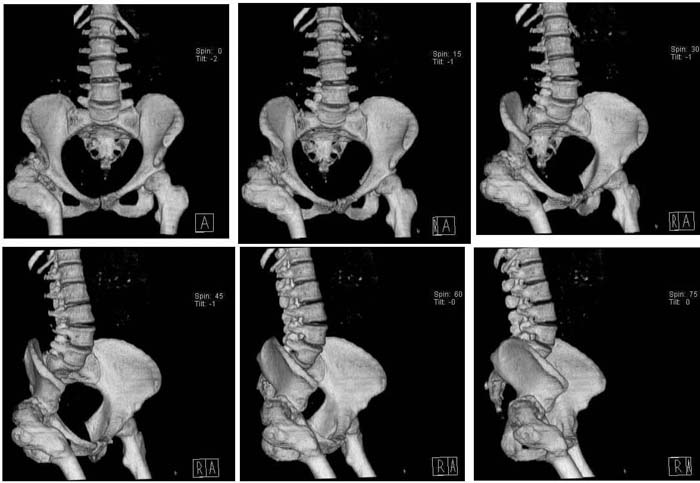

Уважаемые коллеги!Женщина, 35 летВ прошлом по поводу врожденного вывиха бедра перенесла операцию остеотомии по Шанцу

с удлинением правой ноги за счет бедра на уровне диафиза. В последнее время прогрессируют боли в правом тазобедренном суставе, порочное положение правой ноги, затруднена ходьба.Вопросы:1) Целесообразно ли эндопротезирование правого тазобедренного сустава?2) Целесообразный ли следующие действия: канал бедренной кости предполагаем вскрыть для введения ножки протеза на высоте угловой деформации, предполагаем низведение большого вертела с мышцами; протез будет подобран индивидуально, предполагается умеренная версия?В приложении рентгенограммы и трехмерная КТ.В цветном и более качественном варианте КТ размещена здесь